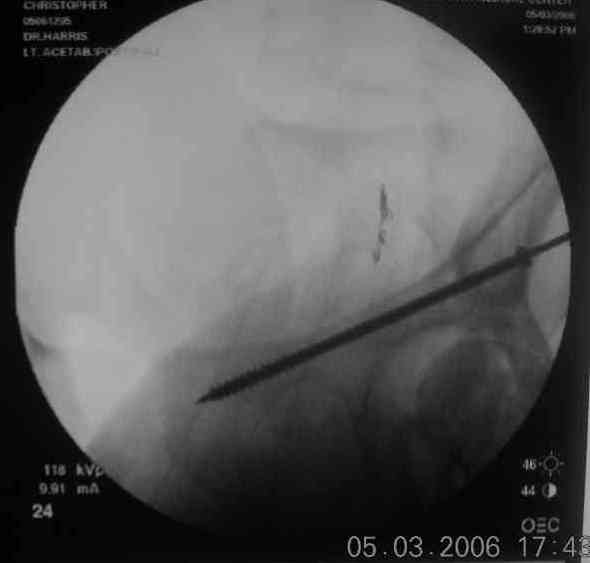

the case that I found is a 20yo male, MCC. his AP pelvis shows an interesting position of his bladder. it is pushed aside by a hematoma from SGA injury. we did a limited lateral window approach for the anterior column first, pt bumped up/supine. then closed and repositioned for KL. I could not find intra-op photos of cases when we did only a small incision for the AC screw (but they do exist!!). the lateral window is available for reduction assessment if a KL approach is being used. in the lateral position this window is available. the prone position definitely takes pressure off of the post column and facilitates reduction. in the lateral position a schantz pin in the ischial tub +/- bone hook in sciatic notch helps with PC reduction. the lateral position also gives better airway access for anesthesia. airway problems are rare, but prone position seems to be a bit more of a challenge to exchange the tube, or reintubate altogether. just something further to debate!